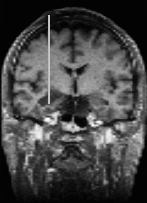

Interventional MR systems allow for a continuous monitoring of the brain typically in a plane through the tip of the intervention device. Whereas a microscope can see only the immediate neighbourhood, interventional MR can look ahead and to the sides which gives more information and security for planning the next step. As the quality and the number of slices generated by an interventional MR is worse than with the preoperative MR, there is a need for registrating and fusing the current slices of the interventional MR with the high quality reference scene.

upper: overview of scull with interventional device and associated scan plane; left: plane from interventional MRI scan (low quality); right: plane from preoperative MRI scan (high quality). Quicktime movie (180 KB) showing positioning of device. |